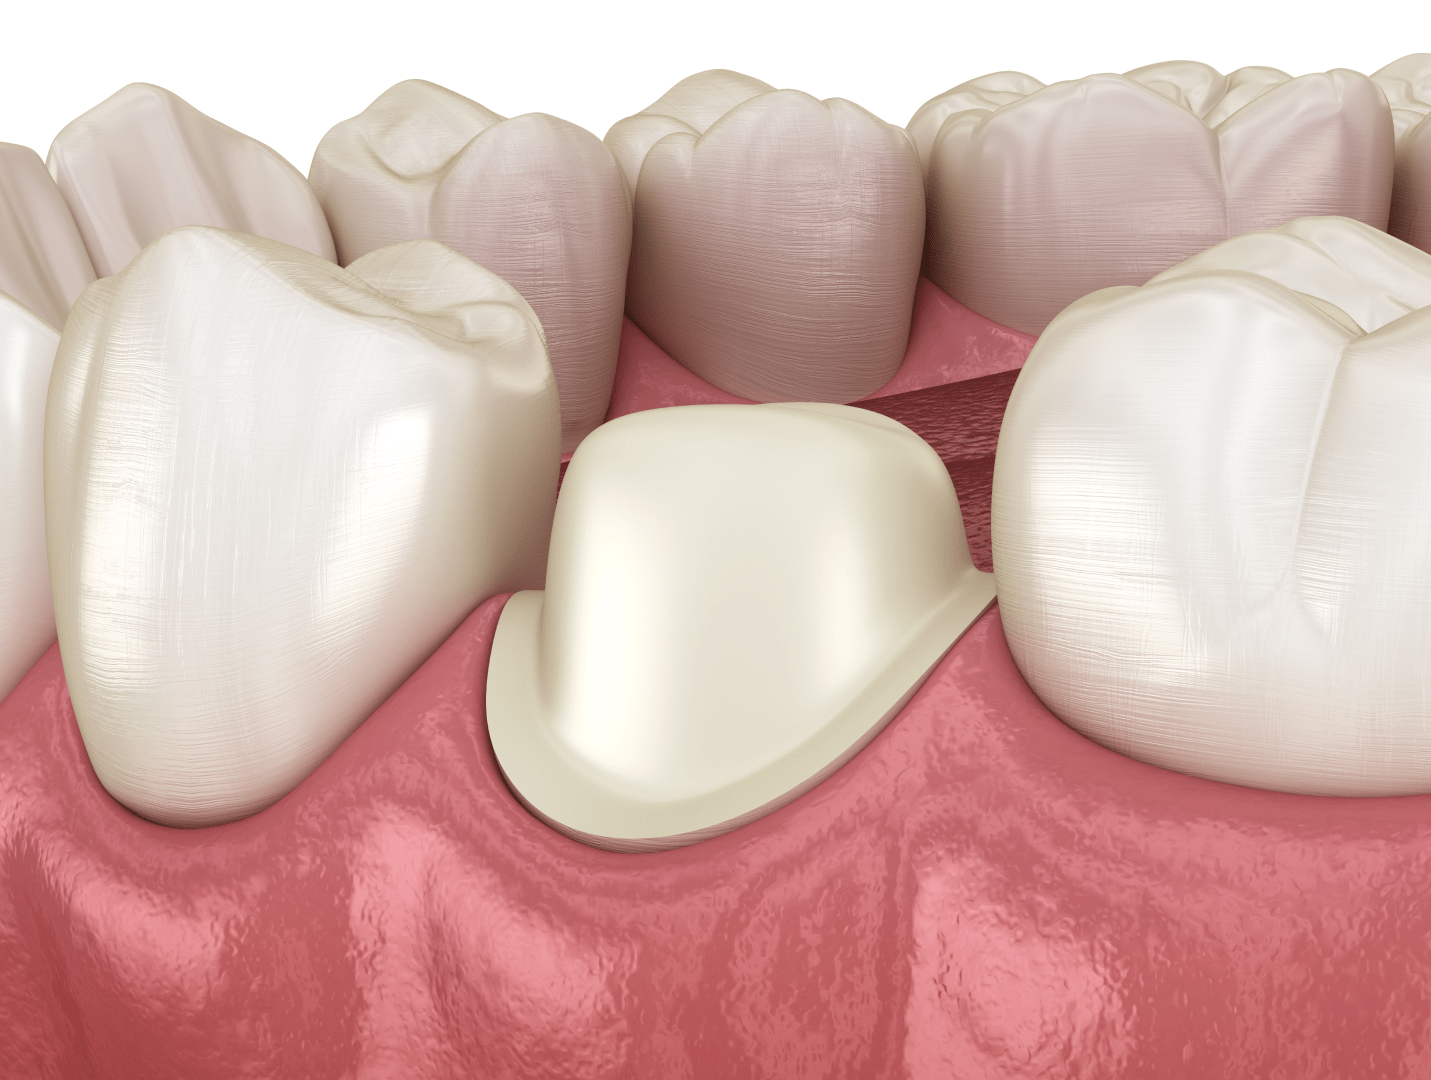

Металокерамічна коронка — це незнімний зубний протез, який встановлюють на попередньо підготовлений (обточений) зуб або фіксують на зубний імплант у разі відсутності природного кореня. Така конструкція використовується для відновлення форми, функції та естетики сильно пошкоджених або втрачених зубних одиниць.

Як відбувається протезування металокерамікою

Металокерамічні коронки в клініці ЦІС зазвичай встановлюються за 2–3 візити до стоматолога. Процедура складається з декількох етапів.